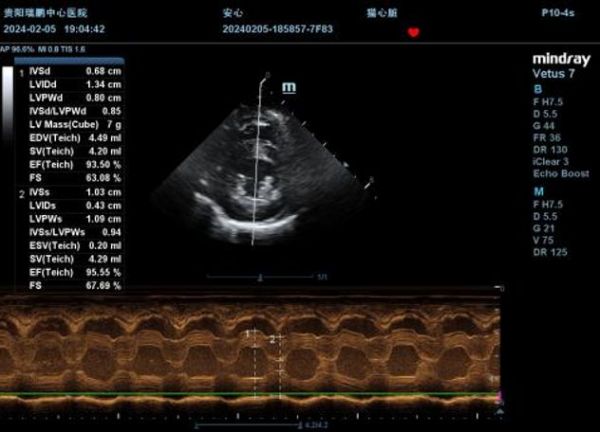

②舒张末期室间隔及左室游离壁厚度超过0.60m(IVSTD:0.68cm、LVPWd:0.80cm),提示猫肥厚型心肌病;结合DR可见肺水肿,提示猫肥厚型心肌病充血性心力衰竭,HCM C期;

③LA/AO=2.36,提示左心房严重扩张,压力、容积过负荷;左心耳扩张,有较大血栓形成风险;

本病例中,患猫通过心脏超声发现心肌明显增厚(0.68cm-0.80cm),左心房扩张(LA/AO=2.36),NT-proBNP显著升高(>1500pmol/l),X线片可见肺水肿,确诊猫肥厚型心肌病,并激发了充血性心力衰竭,在治疗期间患猫出现生化肌酐、尿素氮等肾指标持续升高,最终出现呕吐、厌食等临床症状,在经不断调节补液-利尿之间的平衡之后,将心脏与肾脏二者的交互维持相对稳定水平。根据发病原理可归为1型心肾综合征(急性心肾综合征)。